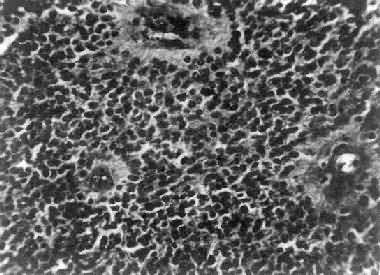

图16-23 星形胶质细胞瘤 左大脑半球肿胀,肿瘤边界不清,部分呈胶冻状 镜下,肿瘤细胞形态多样,可相似于纤维型星形胶质细胞、原浆型星形胶质细胞和肥胖星形胶质细胞,故分别称为纤维型、原浆型和肥胖型星形胶质细胞瘤。前二者为良性肿瘤,后者性质介于良恶性之间。如肿瘤细胞出现间变,细胞密度增大,异型性明显,核深染,出现核分裂像,毛细血管内皮细胞增生,则为间变性星形胶质细胞瘤,为恶性肿瘤。 高度恶性的星形胶质细胞瘤称为多形性胶质母细胞瘤(glioblastoma multiforme),多见于成人。肿瘤好发于额叶、颞叶白质,浸润范围广,常可穿过胼胝体到对侧,呈蝴蝶状生长(图16-24)。瘤体因常有出血坏死而呈红褐色。镜下,细胞密集,异型性明显,可见怪异的单核或多核瘤巨细胞。出血坏死明显,是其区别于间变性星形胶质细胞瘤的特征。毛细血管明显增生,内皮细胞增生、肿大,可导致管腔闭塞和血栓形成。肿瘤发展迅速,预后极差,患者多在2年内死亡。